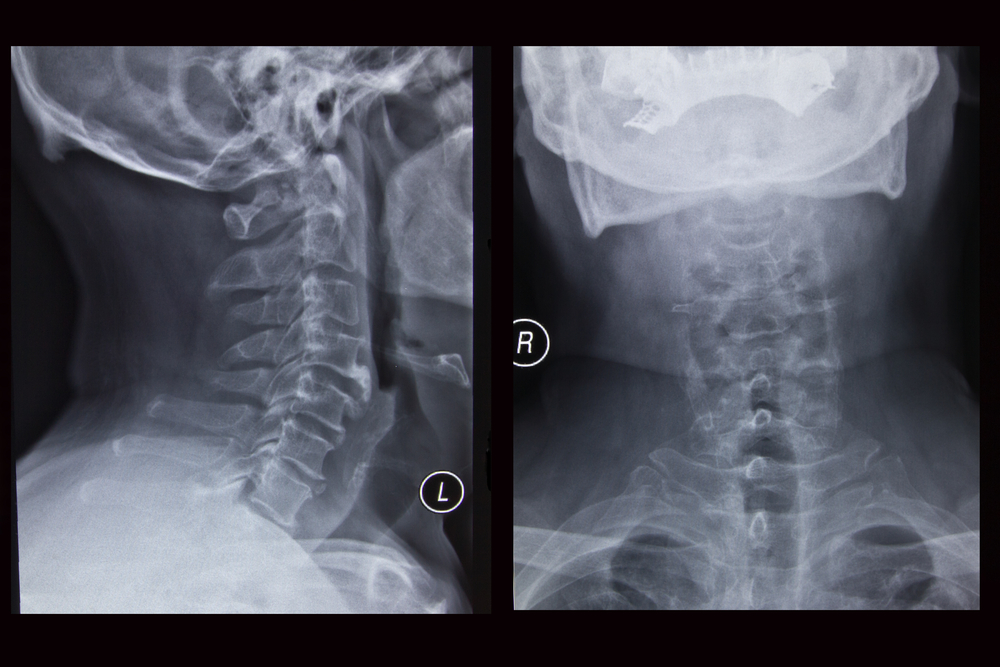

Как и любой диагноз в медицине, диагноз остеохондроза устанавливается на основании жалоб больного, анамнеза заболевания, клинического осмотра и вспомогательных методов исследования. Выполняется рентгенография шейного отдела позвоночника в прямой и боковой проекциях, при необходимости в специальных позициях (с открытым ртом). При этом специалистов интересует высота межпозвоночных дисков, наличие остеофитов. Из современных методов исследования применяются ЯМР и КТ исследования, которые позволяют наиболее точно верифицировать диагноз. Кроме перечисленных методов дополнительного исследования, могут понадобиться консультации смежных специалистов (кардиолога, офтальмолога, нейрохирурга), а осмотр невролога просто жизненно необходим. Лечением остеохондроза занимается невролог, поэтому после осмотра пациента он по своему усмотрению назначит необходимый минимум обследования.